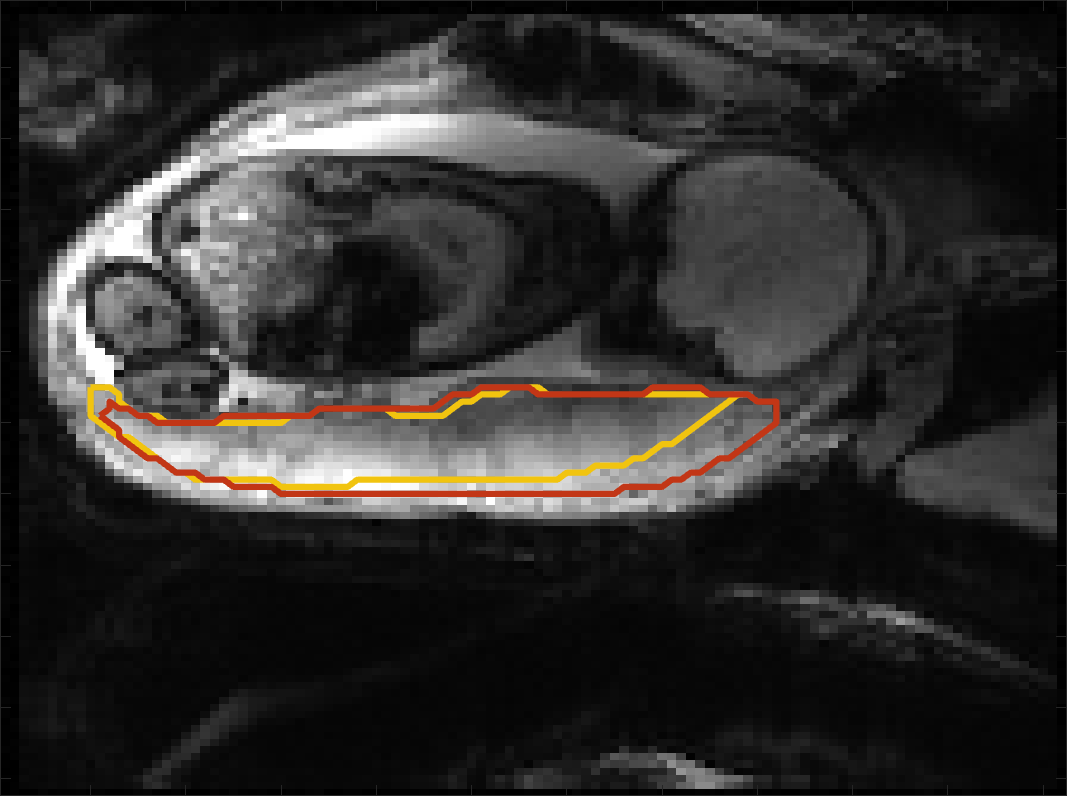

Figure 4 compares the predicted label maps with ground truth on subjects with increasing Dice scores using the BW-CE model. The model accurately identifies the location of the placenta, but in the worst cases misses boundary details.

BOLD Time Series Evaluation

Figure 5 presents example predicted segmentations at multiple points in the BOLD MRI time series for subjects. The predicted segmentations are robust to large fetal deformations and placental signal changes. Figure 6 (top) presents distributions of Dice score between predicted label maps of consecutive frames in the BOLD time series for all subjects in the test set. Distributions have high medians (Dice ) for all but one case, with high density at high Dice scores (Dice ). Dice differences are highly affected by fetal and maternal motion that cause placental deformation. We visually verified that modest drops in Dice () were mainly due to fetal motion, but subjects had a small number of frames with large drops (Dice ) that were caused by errors in the produced label maps. Figure 6 (bottom) shows D models of failed segmentations from two subjects from frames with Dice . Our model omitted parts of the placenta for Subject and added a large region for Subject . In practice, these failures ocurred in a small number of frames, of frames for Subject and of frames for Subject . Overall, predicted label maps are consistent between consecutive volumes of the MRI time series, achieving a Dice of and a BOLD difference of . The small differences between the relative mean-BOLD values suggest these produced segmentations may be suitable for research studies assessing placental function.